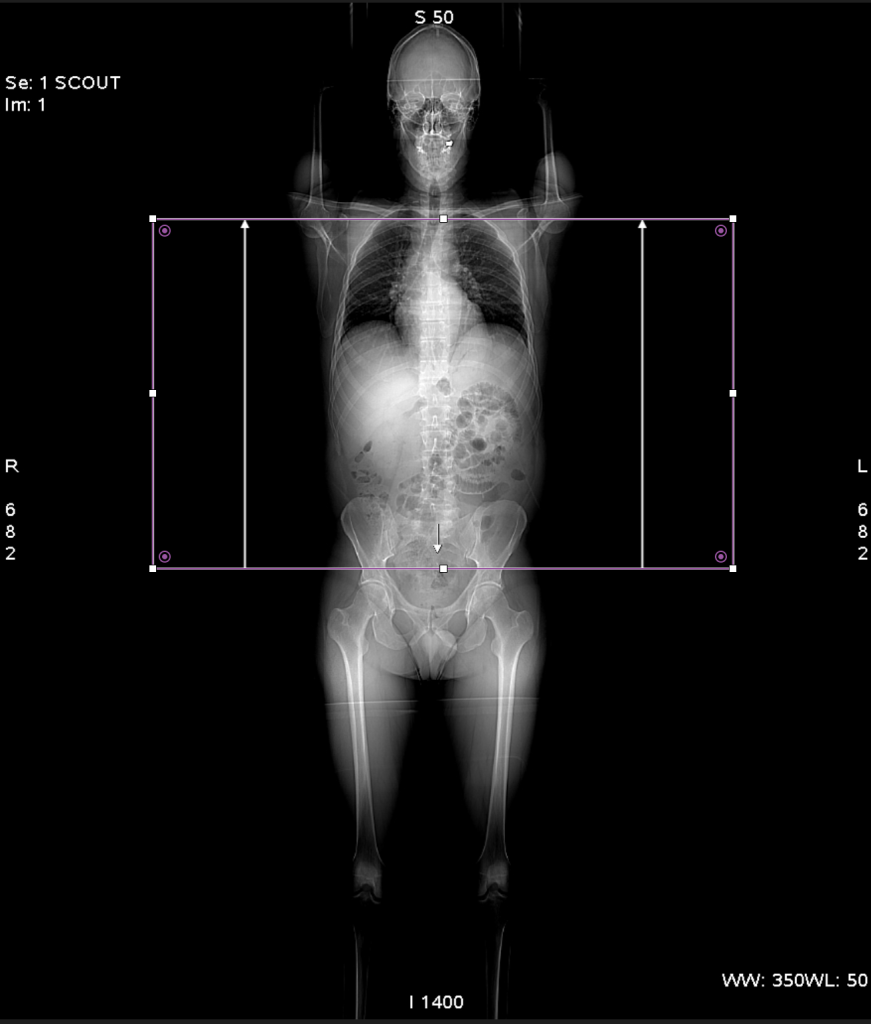

Projection Radiographs

While laser lights in the scanner bore can give a good idea of the centering of the patient and the axial range to scan, 2D imaging is often done before the full 3D CT scan. One or two projection scans are taken to verify positioning and define axial extent of imaging. The x-ray tube is placed either at the top of the gantry for anterior-posterior view, or at the side for a lateral view. With the tube in a fixed position, the bed moves through the scanner for a predefined length and creates a projection image over the distance moved. These initial scans often have different names for different manufacturers and can be referred to as scout scans, topograms, projections, scanograms, or localizers. After these scans, a dialog comes up for the technologist to adjust the axial range to include the desired anatomy.